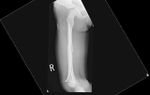

This 4-year old patient presented to the emergency room with a spiral displaced fracture of the right femur. He was running at school and tripped and fell.

He was treated by flexible retrograde intramedullary rods with closed insertion under image guidance with good pos-top results.

His rods will be removed at three months and he is expected to make a full recovery.